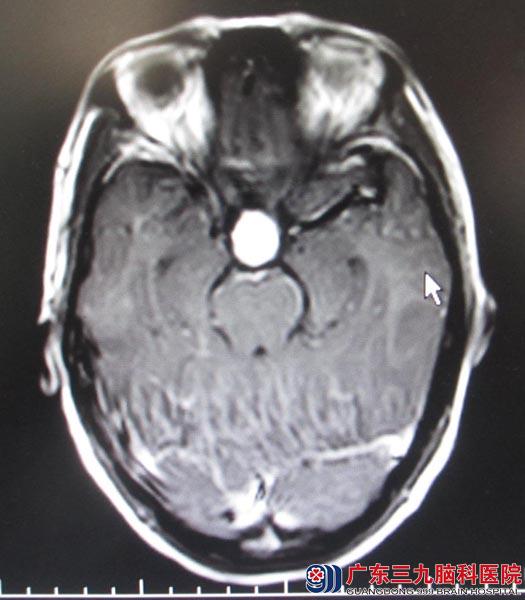

近期吴女士偶发头痛头晕,广东三九脑科医院头颅MRI提示:鞍区占位,入住综合神经外科。头颅MR复查提示“鞍区占位,直径约2.5cm,病灶强化明显,考虑颅咽管瘤与视神经胶质瘤鉴别”。

鲁明主任分析:月经失调一年,伴有双眼视力模糊,参考头颅MR,结合病史,考虑颅咽管瘤可能性大,肿瘤与垂体柄粘连紧密,往上压迫视交叉,手术中容易对垂体柄、视神经、下丘脑等重要结构造成损伤。经过慎重考虑,术前激素替代等周全处理。

▲手术前